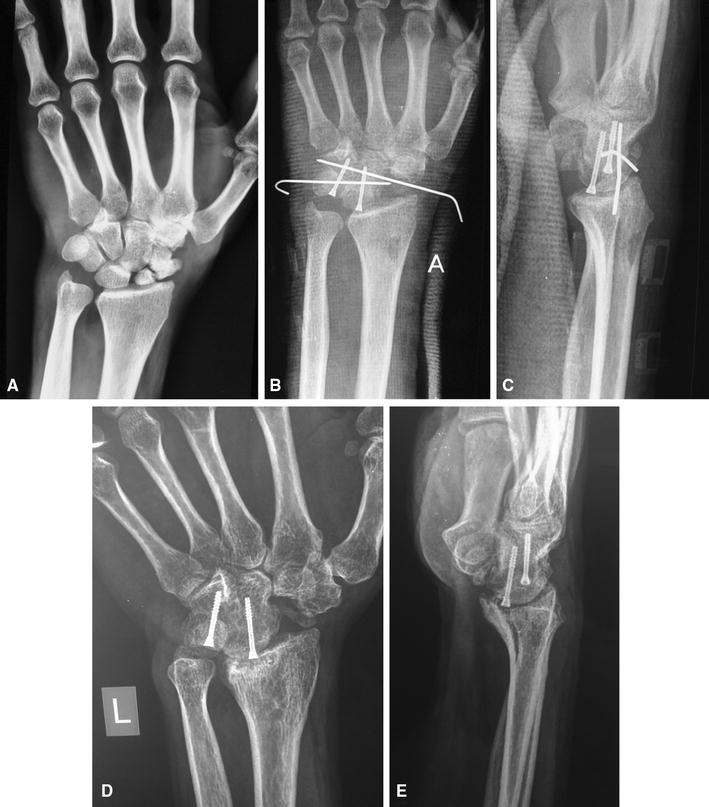

59 Scaphoidectomy and FourCorner Fusion Plastic Surgery Key Four Corner Fusion Xray  Four corner wrist fusion finger trauma metacarpal dcp plating for transverse fracture For his hand fellows and residents professor and consultant of. Partial union is more common with kirschner Four Corner Fusion Xray.

Case example 2 Postoperative (a) AP and (b) lateral radiographs taken Four Corner Fusion Xray  Partial union is more common with kirschner For his hand fellows and residents professor and consultant of. Four corner wrist fusion finger trauma metacarpal dcp plating for transverse fracture Four Corner Fusion Xray.

Wrist with a SNAC III lesion. (A) Final radiograph of fourcorner Four Corner Fusion Xray  Four corner wrist fusion finger trauma metacarpal dcp plating for transverse fracture For his hand fellows and residents professor and consultant of. Partial union is more common with kirschner Four Corner Fusion Xray.